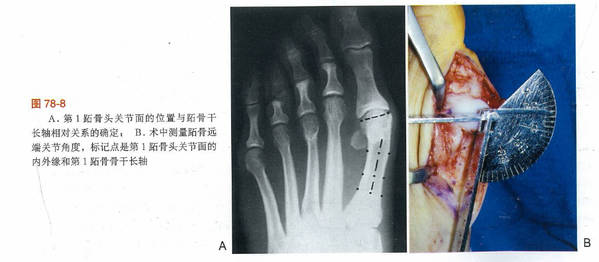

其他两个涉及第一跖趾关节的解剖学改变也可以引起拇外翻

第一个改变为跖骨头关节面偏斜,其偏斜的角度被称为跖骨远端关节固角(DMAA)

2.jpg

1.jpg

第二个改变为趾近节趾骨基底的关节角相对于其纵轴出现偏斜,其偏斜角度被称为趾骨近端关节固角(PAA)